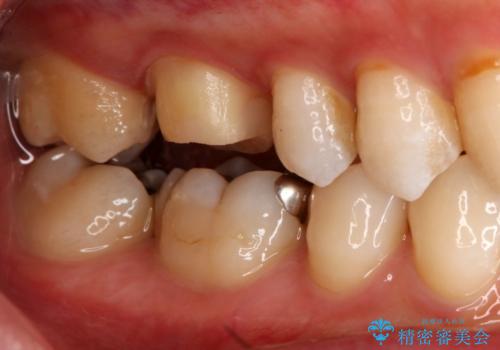

- 右上下6番の銀歯のやり変えを希望された患者様です。

切削量・形態を考慮し、上はセラミッククラウン、下はセラミックインレーでの治療を選択しました。

上はう蝕が歯頚部まで達していたのでクラウンでの治療を選択しました。

銀歯直下もう蝕が進行していたので全て除去した上でCRにて裏層しています。

下はクラウンほど切削量が多くないと判断し、インレーでの治療を選択しました。